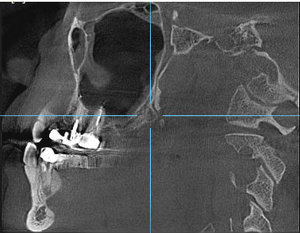

Под новый год заболела челюсть у виска справа (подозреваю, что на фоне проходящего гриппа). Сделал КТ челюсти. Специалистов у нас нет, предложили ехать за консультацией в краевой центр. Можно по снимку определить, что это у меня случилось?

Комментарий №175658 Комментарий №175658 Комментарий №175658 Комментарий №175658

• Описанная проблема может быть связана с височно-нижнечелюстным суставом. Возникнуть симптом может при дегенеративном поражении височно-нижнечелюстного сустава или вследствие других проблем в челюстно-лицевой области (патология прикуса, бруксизм, мышечный гипертонус). Рекомендуем Вам обратиться на консультацию к гнатологу или специалисту в области нейромышечной стоматологии